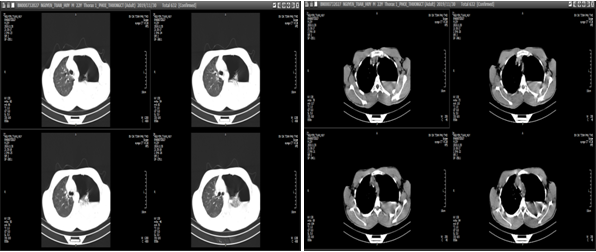

Đước biết trước đó người bệnh khỏe mạnh bình thường và có tiền sử hút thuốc lá 5 năm. Trước lúc vào viện 2 giờ người bệnh đột ngột đau tức ngực trái và khó thở. Người bệnh được chỉ định chụp phim cắt lớp vi tính lồng ngực, kết quả cho thấy: Tràn khí, tràn dịch màng phổi trái.

| Phim chụp cắt lớp vi tính (BVCC). |

BS. Trương Văn Hải - Đơn vị Phẫu thuật Tim Mạch - Lồng ngực - Bệnh viện đa khoa tỉnh Phú Thọ cho biết: Đây là một ca bệnh đặc biệt, hiếm gặp, người bệnh có tràn khí màng phổi tự phát gây xẹp phổi co kéo dẫn đến đứt dây chằng đỉnh phổi chảy máu vào khoang màng phổi.